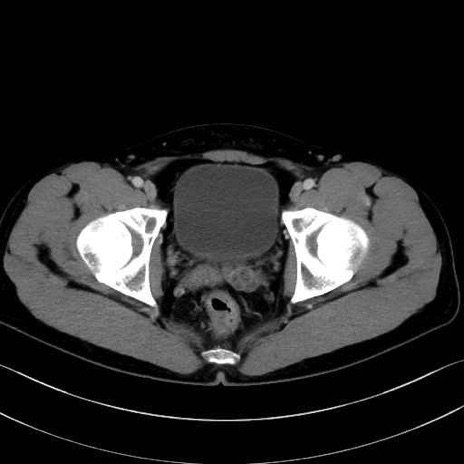

大腿方形筋(Quadratus femoris muscle)のCT画像の解剖

大腿方形筋 (Quadratus femoris)